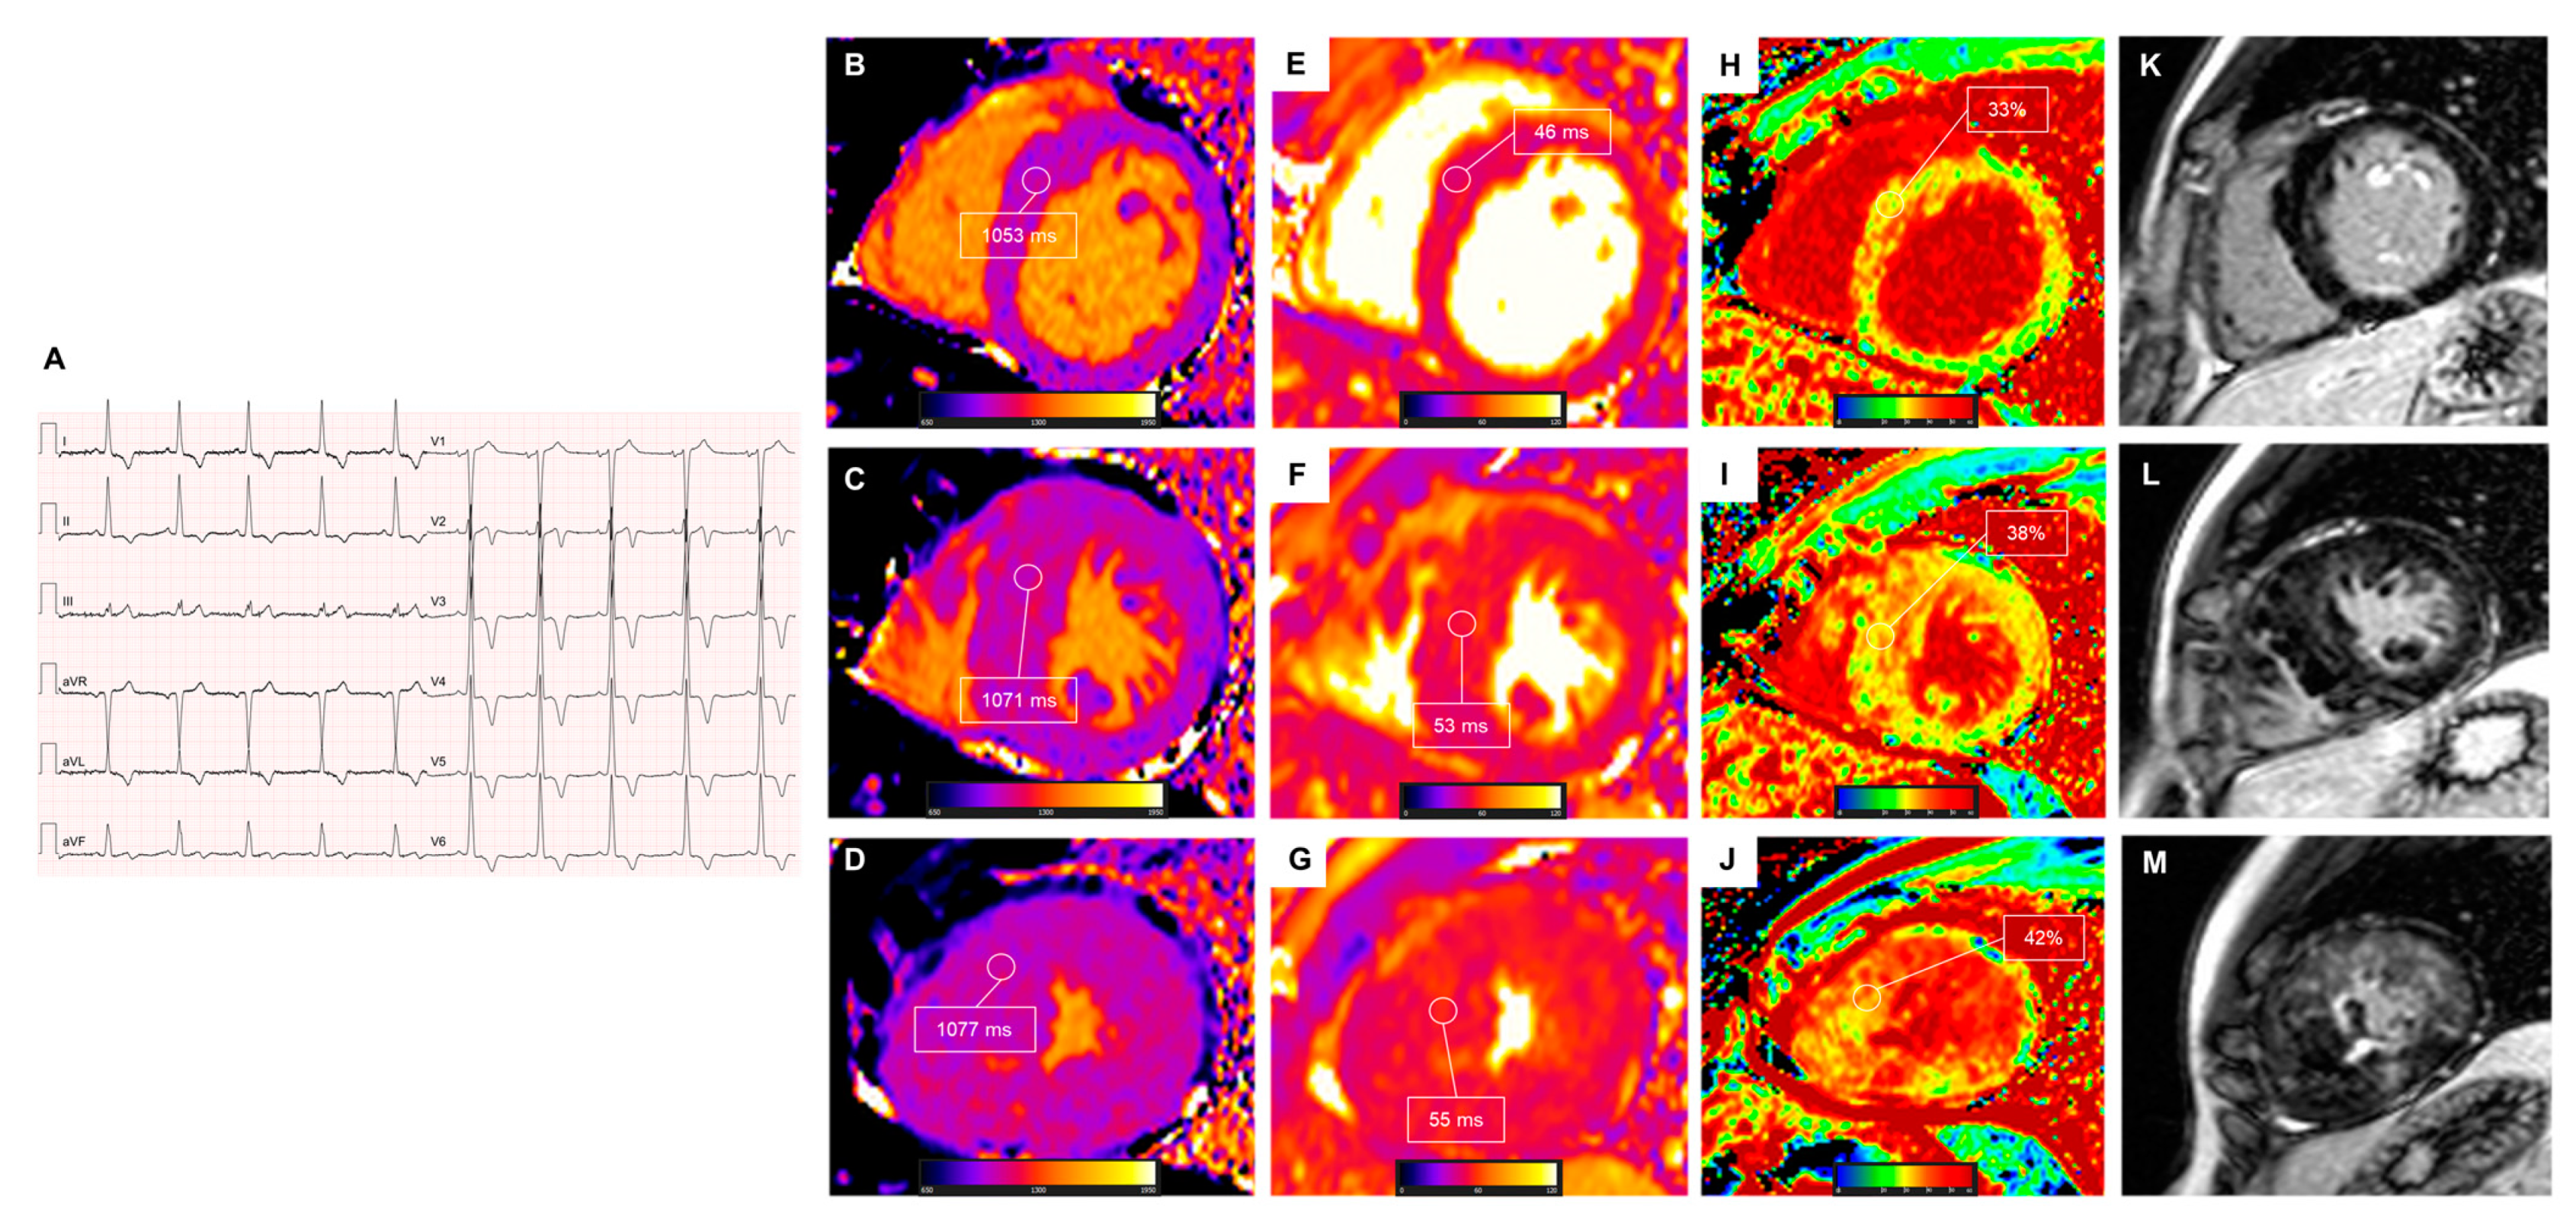

2.4. Dilated Cardiomyopathy

- Li, S.; Zhou, D.; Sirajuddin, A.; He, J.; Xu, J.; Zhuang, B.; Huang, J.; Yin, G.; Fan, X.; Wu, W.; et al. T1 mapping and extracellular volume fraction in dilated cardiomyopathy: A prognosis study. JACC Cardiovasc. Imaging 2022, 15, 578–590. [Google Scholar] [CrossRef]

- Rubiś, P.P.; Dziewięcka, E.M.; Banyś, P.; Urbańczyk-Zawadzka, M.; Krupiński, M.; Mielnik, M.; Łach, J.; Ząbek, A.; Wiśniowska-Śmiałek, S.; Podolec, P.; et al. Extracellular volume is an independent predictor of arrhythmic burden in dilated cardiomyopathy. Sci. Rep. 2021, 11, 24000. [Google Scholar] [CrossRef]